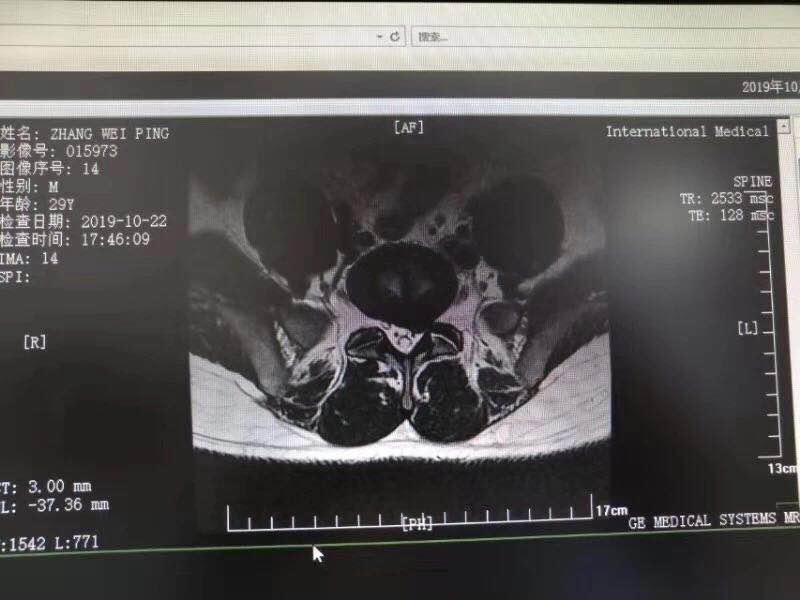

10月28日,西安國際醫(yī)學(xué)中心骨科醫(yī)院脊柱外科成功完成首臺椎間孔鏡手術(shù)。該手術(shù)結(jié)合加速康復(fù)外科(ERAS)理念的精細(xì)化管理和臨床路徑管理,采用微創(chuàng)的孔鏡技術(shù),為解除患者病痛。術(shù)后,患者左下肢放射痛即刻消失,第二天便下床活動鍛煉,已……